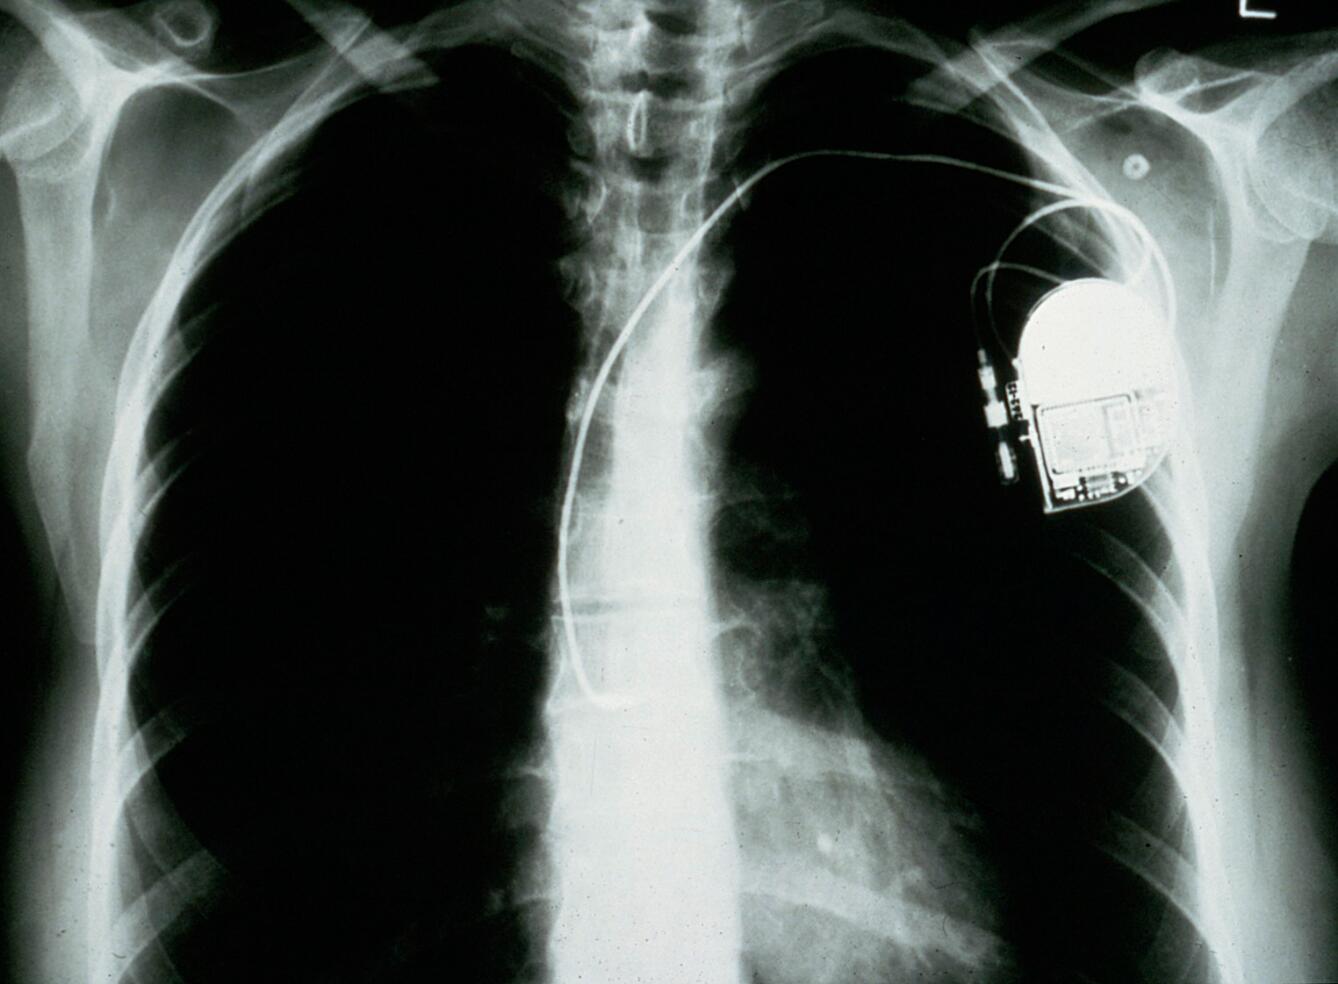

Lifting Weights After Pacemaker Insertion . Only lift heavy objects like your kids, animals, or weights once we clear you. Damage to the pacemaker can result in serious health complications to the heart, which will require immediate medical care and/or. It's essential to avoid raising the arm on the side of the pacemaker to prevent complications. After a pacemaker insertion, staying away from strenuous exercise or activity is crucial until we clear you. You should avoid carrying out any strenuous activity for at least two. The good news is that, in most cases, individuals with pacemakers can safely engage in weightlifting and strength training exercises. ° slowly increase how much you lift and how often ° avoid straining or holding your breath when lifting. I lift the stools from storage onto pallets, from pallets to table saw, from saw to work tables, from work tables back to pallets. However, it is crucial to consult with your healthcare provider before starting or modifying any exercise program. Although resistance training is recommended for maintaining strong muscles and bones, people with pacemakers need to be cautious about lifting heavy weights. Most common household electrical equipment, such as hairdryers and microwave ovens, will not be a problem, as long as you use them at least 15cm. Can i lift weights with a pacemaker? It is also important to avoid lifting weights (such as shopping bags, garden rubbish) for the first six weeks after the procedure. Hand weights, resistance bands, weight machines, or your. In fact, it's best to avoid heavy weightlifting, especially in the upper body, dr.